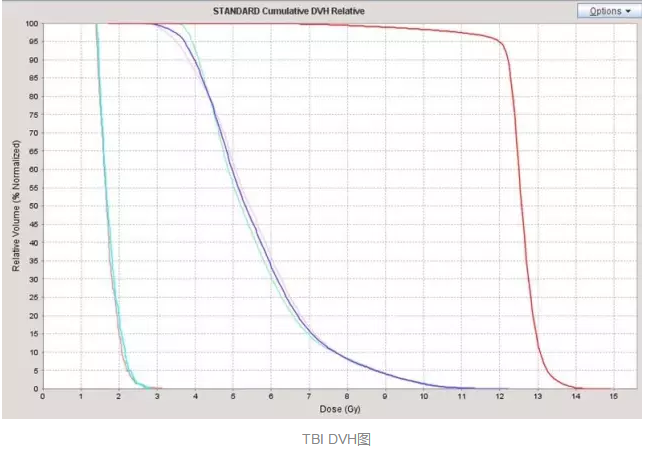

еңЁе®һйӘҢйғ‘еӨ§дёҖйҷ„йҷўйҰ–дҫӢ TBI зҡ„еҺҶзЁӢдёӯ����пјҢж”ҫе°„жІ»з–—йғЁжқҺеӣҪж–Үдё»д»»и®Өзңҹ TBI зҡ„ж•ҙдёӘжүӢиүәжөҒзЁӢ����пјҢйғӯи·ғдҝЎеүҜдё»д»»иҜҰз»Ҷи®Өзңҹе®һйӘҢдёҺеҢ…з®Ў����пјҢеҢ»з”ҹз»„еј ж—ӯдёңеҢ»з”ҹйҳ…иҜ»зӣёе…іж–ҮзҢ®����пјҢ并дәІиҮӘеҲ°ејҖеұ•иҜҘжүӢиүәйўҶе…Ҳзҡ„е№ҝе·һеҶӣеҢәжҖ»еҢ»йҷўж”ҫ疗科еӯҰд№ ����пјҢиҜҘйҷўж”ҫ疗科й»Һйқҷдё»д»»зҡ„ж”ҫз–—еӣўйҳҹз»ҷдәҲдәҶж— з§Ғзҡ„йјҺеҠӣеӨ§дёҫиө„еҠ©���пјӣзү©зҗҶз»„з»„й•ҝ马йҳіе…үеҗ‘еҜјзү©зҗҶз»„е…ЁдҪ“иҒҢе‘ҳиө·еҠІеҚҸи°ғ����пјҢзҺӢжө·жҙӢзү©зҗҶеёҲдҪҝз”Ёе‘ЁеӨ©дј‘жҒҜзҡ„ж—¶й—ҙдёҫиЎҢиҙЁйҮҸжҺ§еҲ¶жқҘзЎ®���пјӣйўҠе’§зҳҹзІ•зі»йӮЈеҜ°���пјӣжүӢиүәз»„з»„й•ҝжӣ№дҝҠеҚҺеҗ‘еҜјжүӢиүәз»„е…ЁдҪ“жҲҗе‘ҳж”»еқҡе…Ӣйҡҫ����пјҢжңҖз»ҲеңЁеҗ„дёӘйғЁеҲҶзҡ„й…ҚеҗҲиө·еҠІдёӢ����пјҢ2016 е№ҙ 5 жңҲ 16 ж—Ҙйғ‘е·һеӨ§еӯҰ第дёҖйҡ¶еұһеҢ»йҷўйҰ–дҫӢ TBI жІ»з–—е®ҢжҲҗ����пјҢз”ұдәҺж”ҫе°„жІ»з–—йғЁдҪҝз”Ё TOMO HD еҠ йҖҹеҷЁе®һйӘҢзҡ„ TBI ����пјҢеүӮйҮҸжј«иЎҚеҚҒеҲҶе®Ңе–„пјҲеҰӮдёӢеӣҫжүҖзӨәпјү����пјҢзұ»дјјй•ҢеҲ»����пјҢд»ҘжҳҜеҸҲиў«з§°дёәгҖҢй•ҢеҲ»ејҸе…Ёиә«ж”ҫз–—гҖҚ����гҖӮ